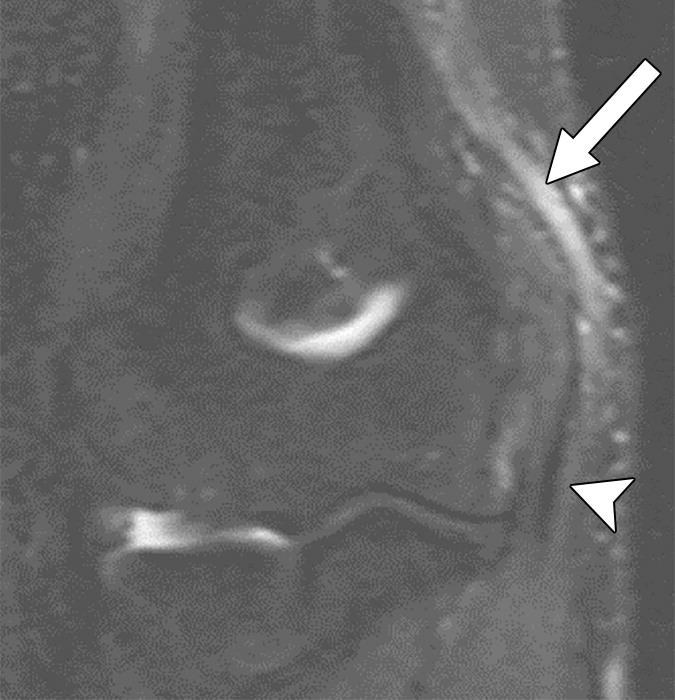

Our retrospective study included 100 patients with nerve imaging examinations and a variety of known clinical diagnoses. Utilizing mutually agreed-upon qualitative benchmarks for classifying and grading peripheral neuropathies, different classes were established to account for the spectrum of underlying pathologies (unremarkable, injury, neoplasia, entrapment, diffuse neuropathy, not otherwise specified, and postintervention state) with subclasses to describe lesion severity or extent. Validation was performed by 11 fellowship-trained musculoskeletal radiologists across 10 institutions, and after initial multimedia training, all 100 cases were blind-presented to readers (Fig. 1).

Offering a uniform lexicon and practical guideline for reporting neuropathic conditions on MRI, ultimately, NS-RADS accuracy for determining milder versus more severe categories per radiologist ranged from 88% to 97% for nerve lesions and from 86% to 94% for muscle abnormalities (Fig. 2).